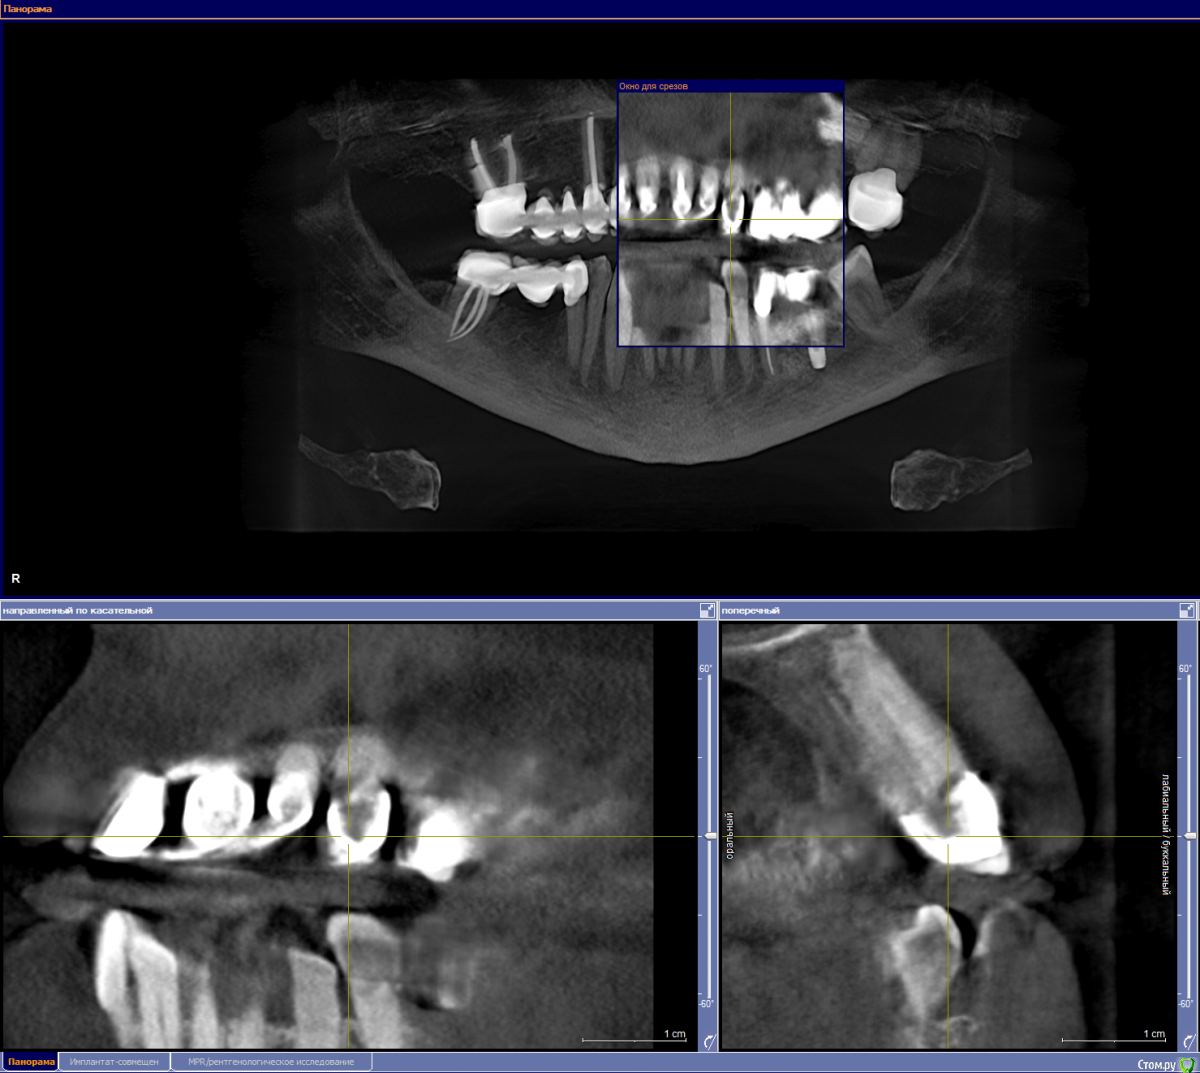

ellenchik Опубликовано 3 мая, 2018 Автор Поделиться Опубликовано 3 мая, 2018 Уважаемые Доктора! Я снова к Вам с просьбой. Продолжу мою тему.После депульпирования 21 зуба, боль в области трех обозначенных на снимке верхних передних зубов осталась прежней. Появляется спонтанно в любое время. На перкуссию - спокойно. Боль жгучая,ноющая,разлитая.Иногда отдает в переносицу. Врач говорит,возможно у зуба № 2 большая пломба давит на нерв. Я ощущаю часто боль в зубе № 3. Несколько дней может быть всё спокойно. Принимаю Ибупрофен 400. Иногда помогает иногда нет. Ощущение,что болят эти 3 зуба. Конкретно уже не могу сказать. Будучи проездом в Питере ,сделала 3 Д томографию,но только диск без описания, к врачу не попала, к сожалению. Здесь врач (в Германии в маленьком городке ) с этим не работает. Посмотрите ,пожалуйста, общий срез-снимок. Зубы 1-2-3. Номер 1 депульпирован в январе, как предполагаемый источник проблемы и боли. Подскажите,пожалуйста, какие срезы сделать и выложить для бОльшей информативности. Очень надеюсь на Вашу помощь. Спасибо всем откликнувшимся. С уважением Елена Ссылка на комментарий

ellenchik Опубликовано 5 мая, 2018 Автор Поделиться Опубликовано 5 мая, 2018 kramer, спасибо за ответ.Срез сделала,но не уверена, что правильно. Подскажите,пожалуйста, если что не так. Буду делать другие. Ссылка на комментарий

ellenchik Опубликовано 7 мая, 2018 Автор Поделиться Опубликовано 7 мая, 2018 ...похоже, я неправильно делаю срезы :-( Подскажите, пожалуйста. Тема по прежнему актуальна. Мой врач предположил, что есть воспаление у зуба № 1 (отмечен на снимке) и предлагает глубокую хирургическую чистку (вероятно резекцию корня) Хотелось бы услышать еще мнения уважаемых докторов. Ссылка на комментарий

ellenchik Опубликовано 31 января, 2019 Автор Поделиться Опубликовано 31 января, 2019 Уважаемые доктора! Подниму свою старую тему, т.к. актуальна. Летом 2018 была у 2-х врачей на консультации. Ничего не нашли. Последние 3 недели снова обострились непонятные боли слева в районе 1-2-3 зубов. Но теперь больше над зубом № 3, именно НАД зубом - отдает вверх в переносицу . Такая разлитая ,жгучая,колющая боль. На холодное-горячее вроде как не реагирует. Болит спонтанно и ночью тоже. Врач смотрела - ничего не находит. Делала какую-то пробу над этим зубом чем-то типа бора - жужжащим приборчиком . Было прилично больно,как по нерву. Сказала,что это неплохо. По рентгену тоже говорит всё ОК. Свежий рентген прилагаю.Посмотрите пожалуйста. Есть еще КТ апреля 2018 в формате GALILEOS Viewer фирмы Sirona Dental SystemsВот ссылка https://dropmefiles.com/5XIaY (Эта проблема была уже тогда) Была бы очень признательна,если бы кто-нибудь глянул. С уважением Елена Ссылка на комментарий

ellenchik Опубликовано 2 февраля, 2019 Автор Поделиться Опубликовано 2 февраля, 2019 Подскажите, плииз, дорогие доктора, возможно ли в моем случае что-то увидеть по КТ? Или снимать все 3 коронки и смотреть по ситуации? При консультации у 3-х врачей - мнения разные. 1). Делать резекцию зуба № 1 , т.к. после удаления нерва боль осталась прежней и возможно воспаление. 2). подозревает, что у зуба № 2 пломба стоит близко к нерву и возможно давит на него и в этом причина. 3) маловероятно, но возможно это зуб № 3, хотя там даже и кариеса не было.Но в последнее время разлитая, жгучая, ноющая боль как будто в корне этого зуба № 3. Уже и не знаю к какому врачу пойти. Но и удалять нервы в оставшихся зубах на удачу, тоже не хочется. С первым зубом уже не повезло. Буду очень рада любому мнению. С уважением ЕленаВ среду опять на прием-сделаю еще прицельный этих 3-х зубов. Может что-то еще сделать,подскажите, плииз... Ссылка на комментарий